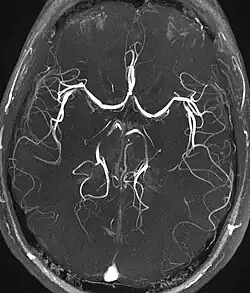

Magnetresonanzangiographie

Die Magnetresonanzangiographie (MR-Angiographie, MRA) ist ein bildgebendes Verfahren zur diagnostischen Darstellung von Blutgefäßen (Arterien und Venen) mit den Methoden der Magnetresonanztomographie (MRT). Zu diesem Zweck können unterschiedliche Techniken eingesetzt werden, die zum Teil vollständig nicht-invasiv sind (also ohne operative Eingriffe und Injektionen auskommen) oder auf der Gabe von MRT-Kontrastmittel basieren. Im Gegensatz zur konventionellen Angiographie werden anstelle von zweidimensionalen Projektionsbildern bei der MRA im Regelfall dreidimensionale Datensätze aufgenommen, die eine Beurteilung der Gefäße aus allen Blickrichtungen ermöglichen. Ein weiterer Unterschied zur konventionellen Angiographie ist, dass bei der MRA kein Katheter in das Blutgefäßsystem eingeführt werden muss. In vielen Bereichen ist die MRA ein zu digitaler Subtraktionsangiographie, CT-Angiographie und Sonographie konkurrierendes Verfahren.[1][2]

Die Time-of-Flight-MRA (TOF-MRA) nutzt aus, dass frisch einströmendes Blut im Untersuchungsvolumen eine höhere Magnetisierung aufweist, als das stationäre Gewebe, dessen Magnetisierung durch die einwirkenden HF-Pulse der MRT-Pulssequenz reduziert (gesättigt) wird. Die Blutgefäße mit frisch einströmendem Blut werden daher signalreich dargestellt. Für die TOF-MRA werden gewöhnlich schnelle 2D- oder 3D-Gradientenecho-Techniken (FLASH) eingesetzt; es wird kein Kontrastmittel benötigt.